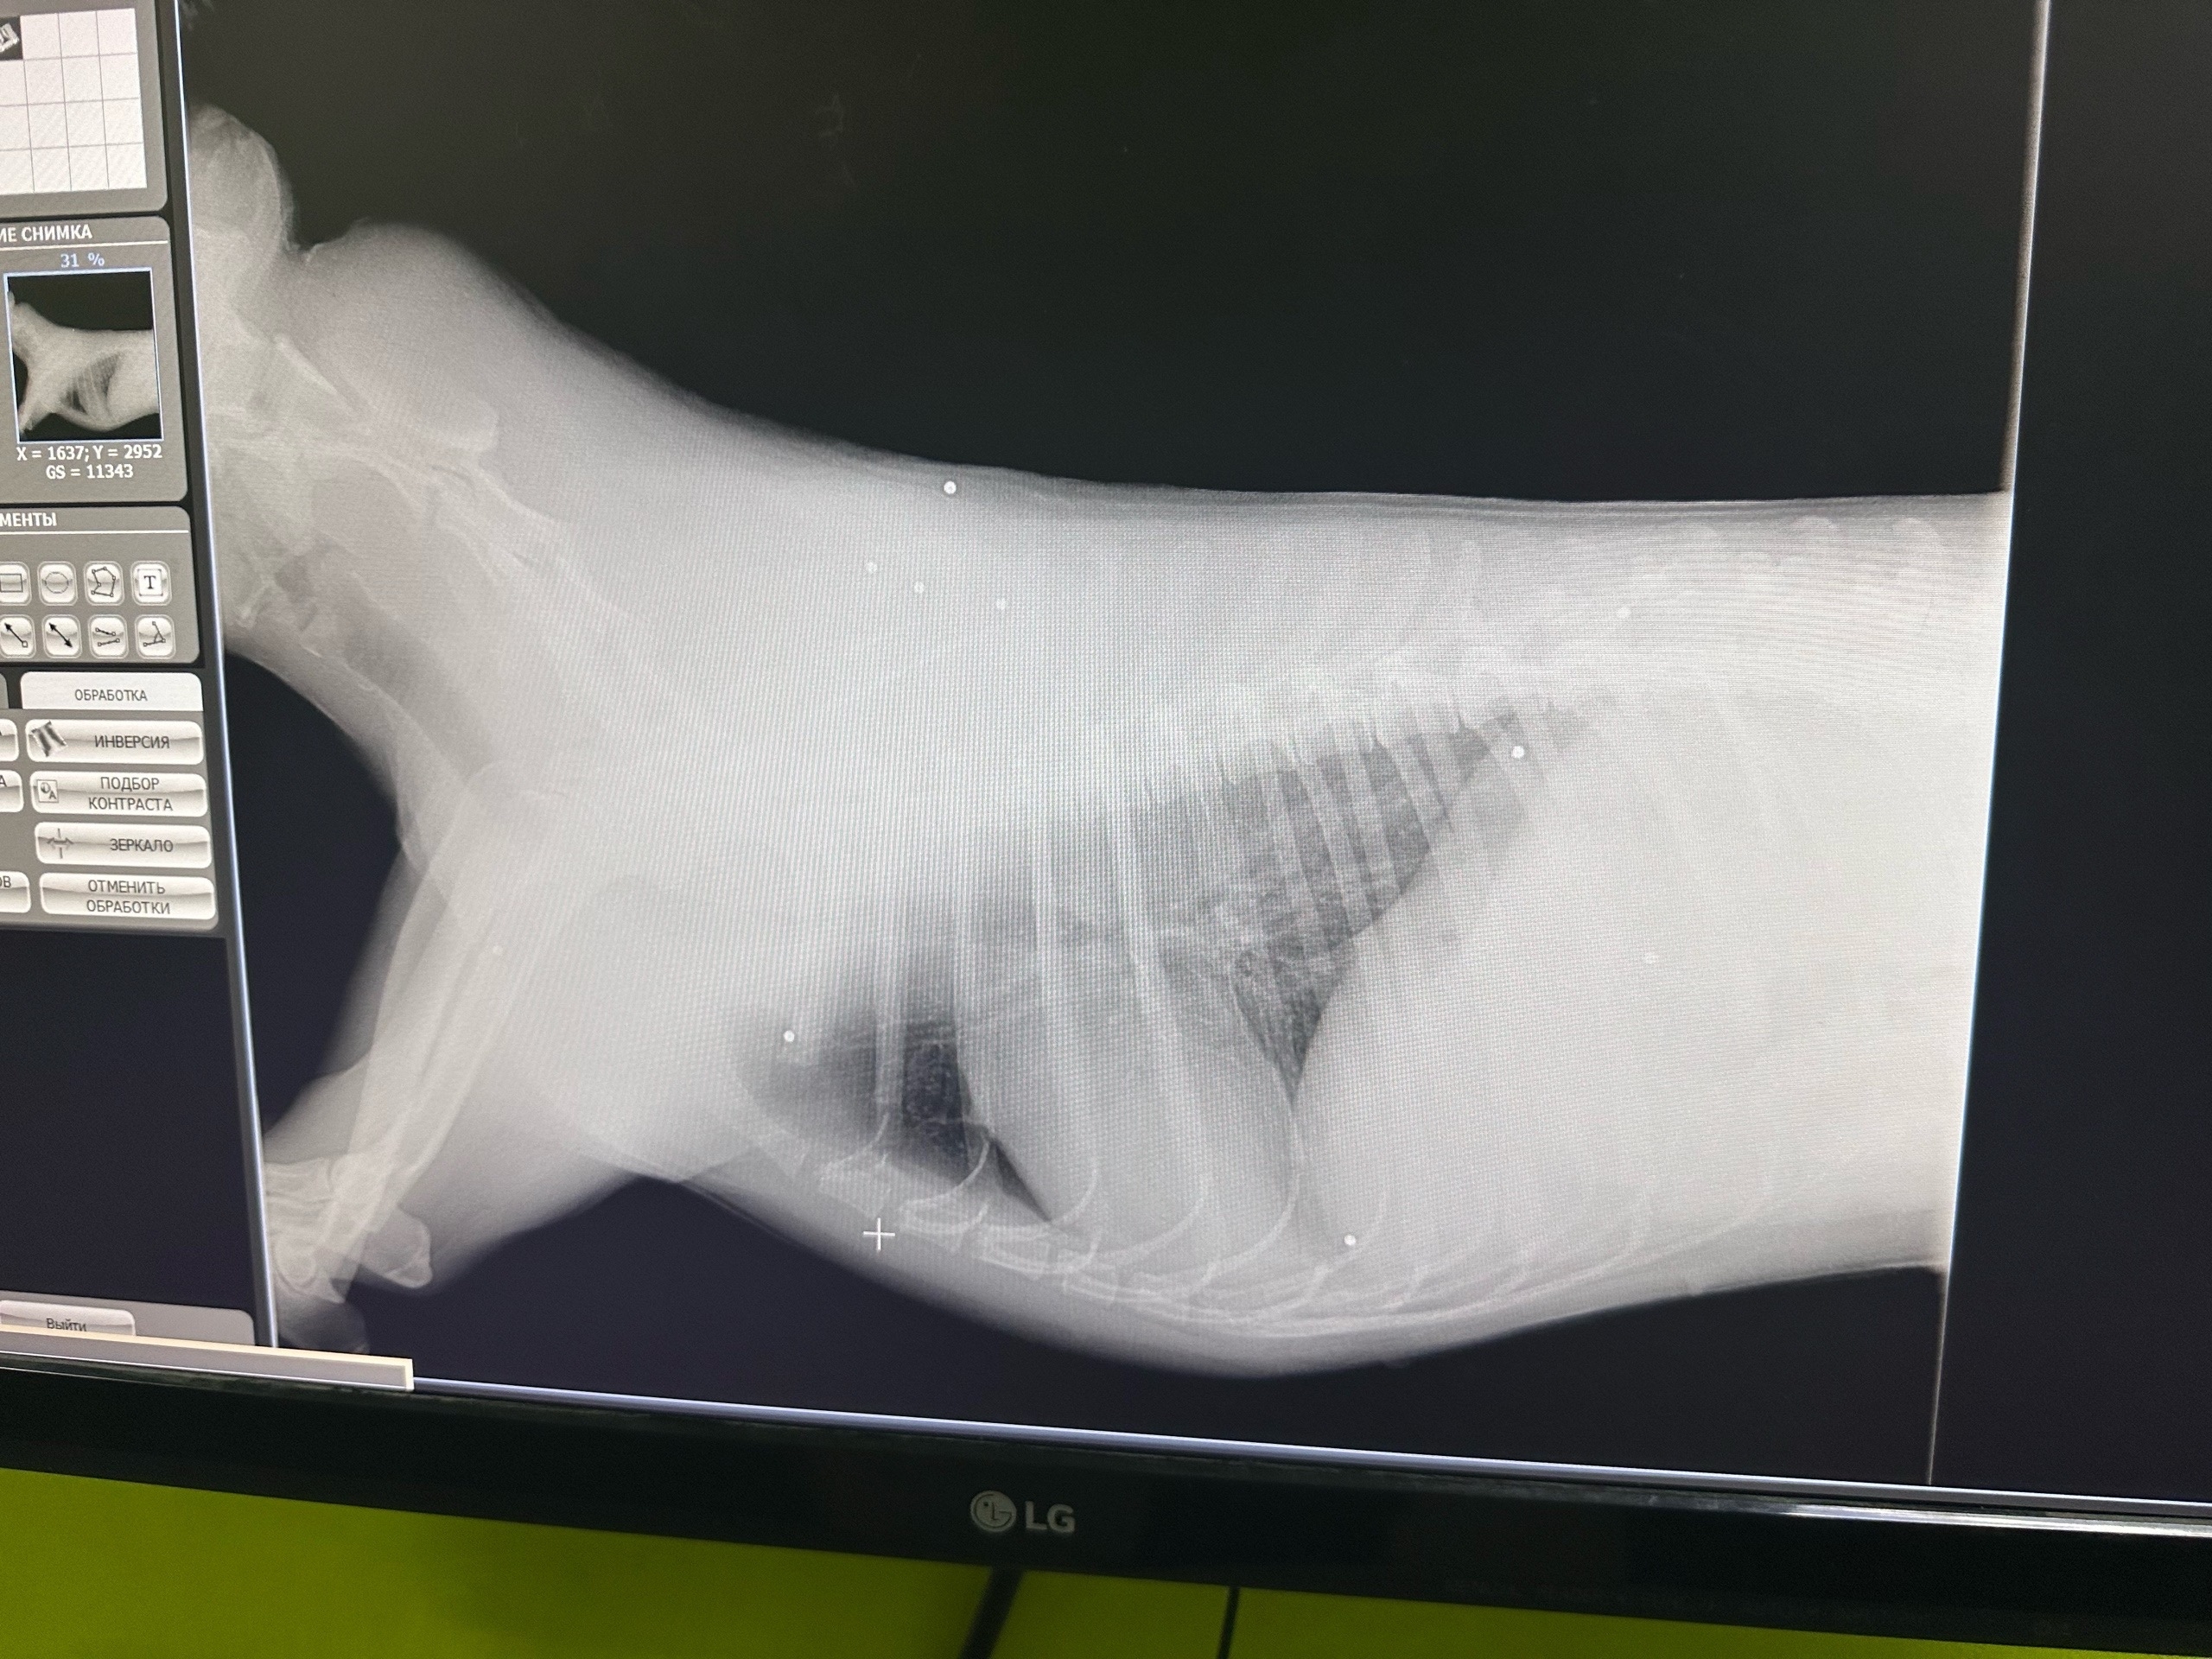

Врачи установили, что животному выстрелили в голову, а дробь разошлась по спине и телу.

Врачи установили, что собаке выстрелили в голову, а дробь разошлась по спине и телу. Сейчас собака по кличке Умка находится в тяжёлом состоянии в стационаре. У неё отсутствует чувствительность задних лап, степень повреждения позвоночника пока остаётся неясной. Сколько времени животное провело на морозе с огнестрельными ранениями, неизвестно.